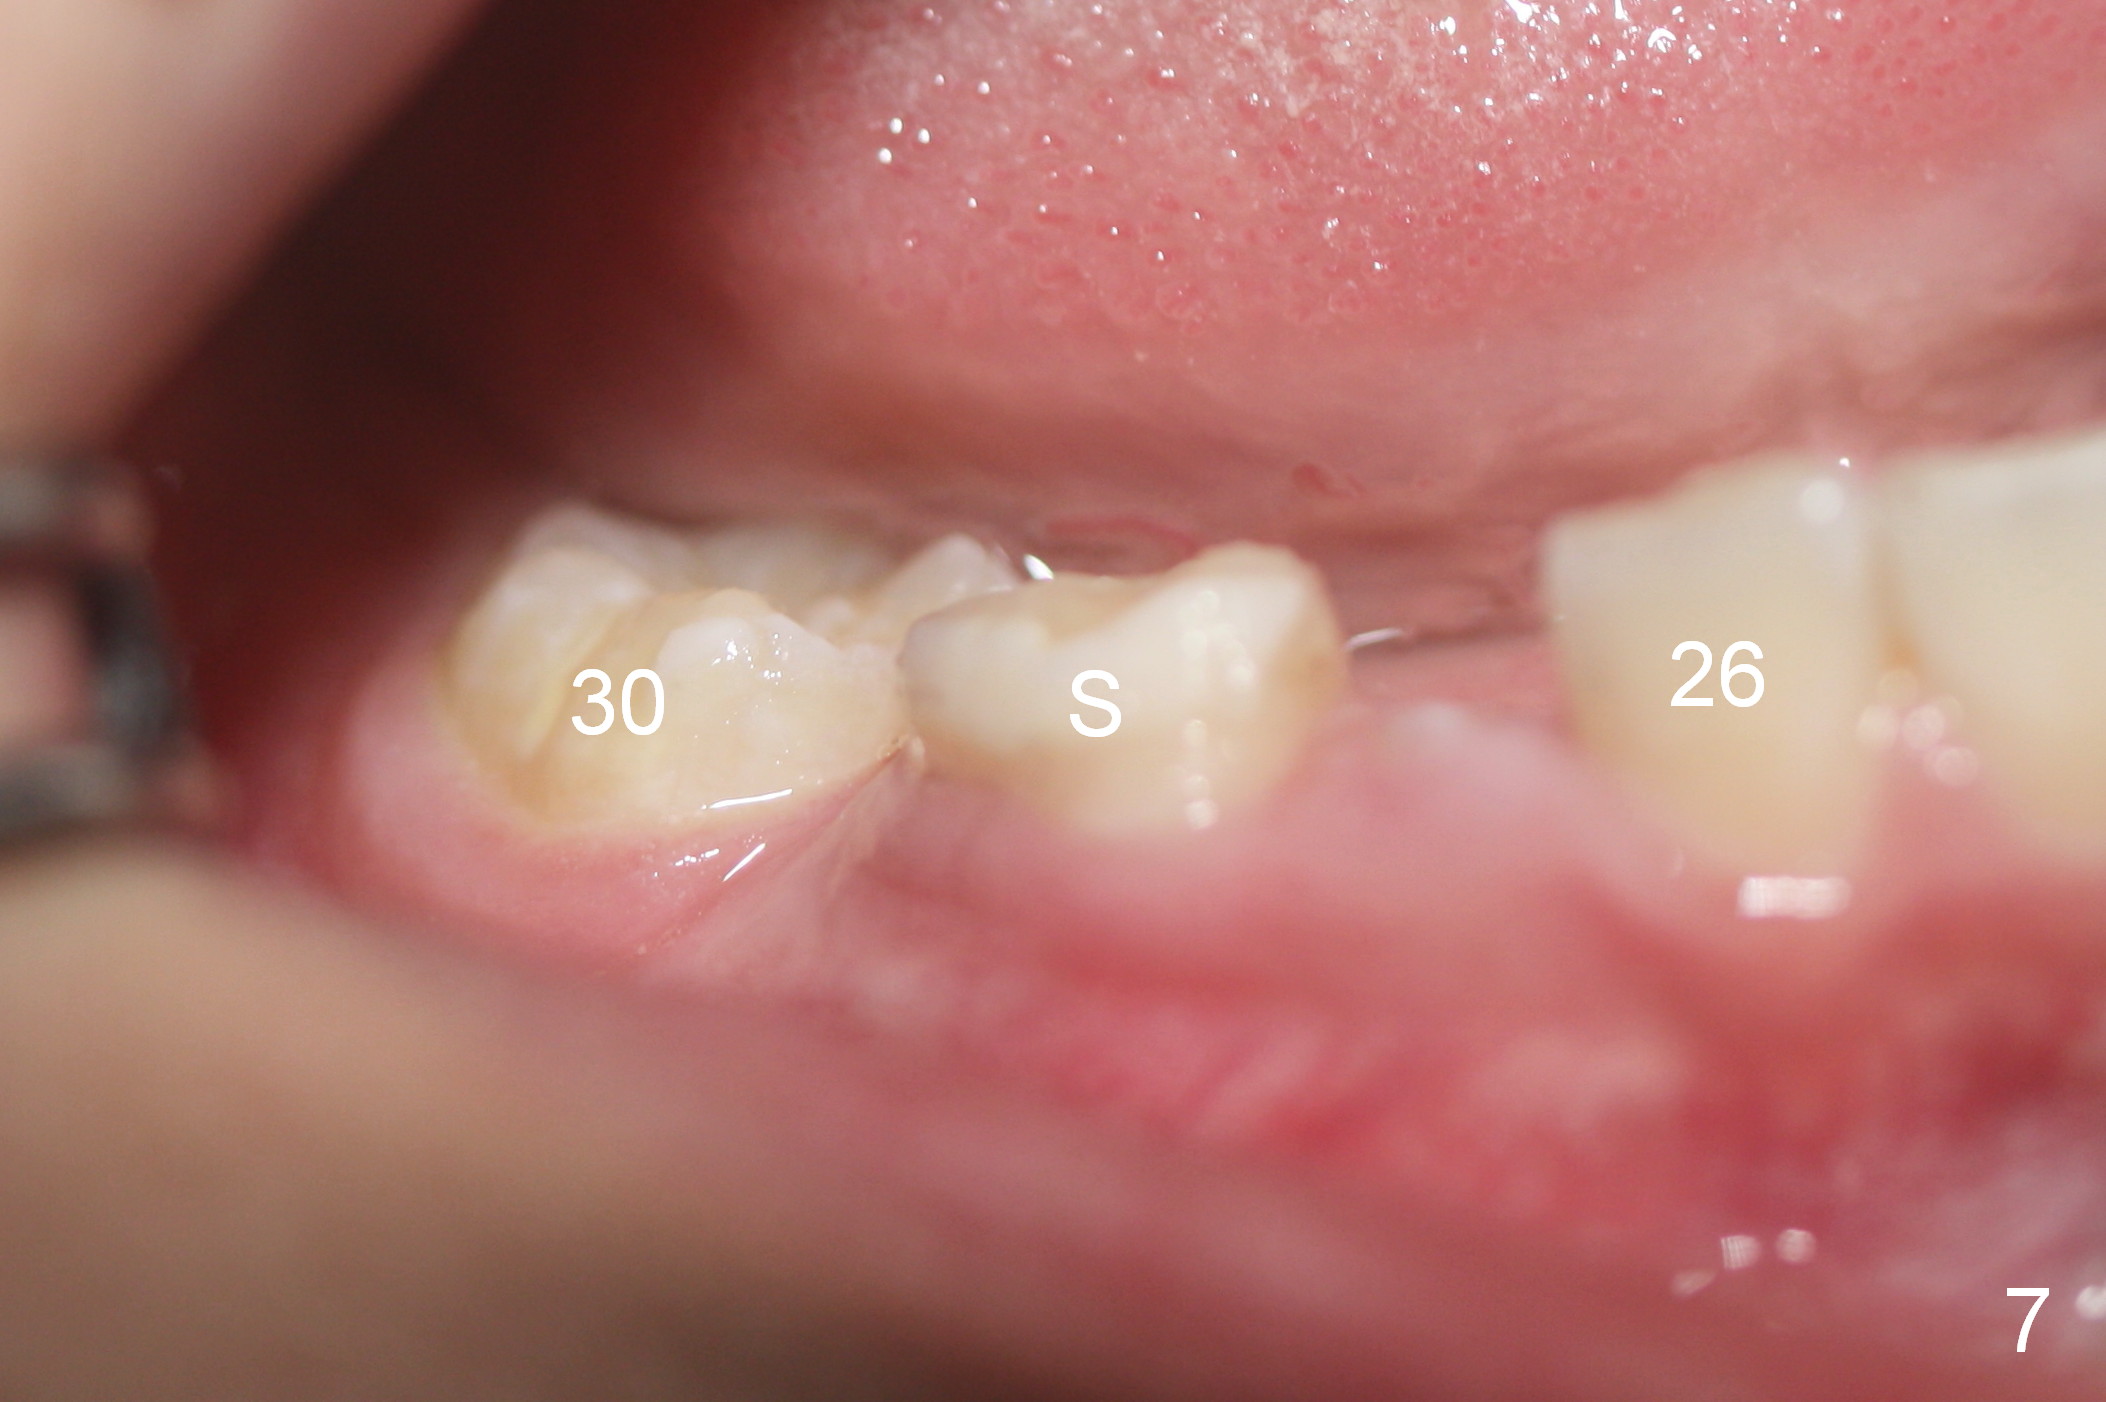

At age of 6 years 1 month, Linwei (boy) has crowding problem, especially in the lower right quadrant (Fig.1). At 9, the crowding also involves the upper right and lower left quadrants (Fig.2). A bilateral space regainer is placed for the lower arch a month later.

In 3 months, space has gained at J and T. Due to mobility of S, the space regainer is removed; a space maintenance is placed J (Fig.3 (9 years 4 months old)). The tooth #22 is erupting.

One month later, the tooth #5 erupts more (Fig.5,6) and is extracted (Fig.8-10). The tooth S is to be extracted to make room for #27 and 28 eruption (Fig.7).